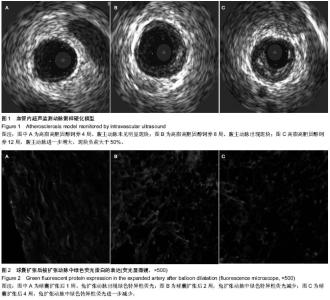

Wei Gang, Gao Shangyuan, Zhang Ying, Huang Weiyi.

Immunostimulation combined with liquid nitrogen freezing to construct a rat model of atherosclerotic vulnerable plaque

[J]. Chinese Journal of Tissue Engineering Research, 2020, 24(35): 5656-5661.